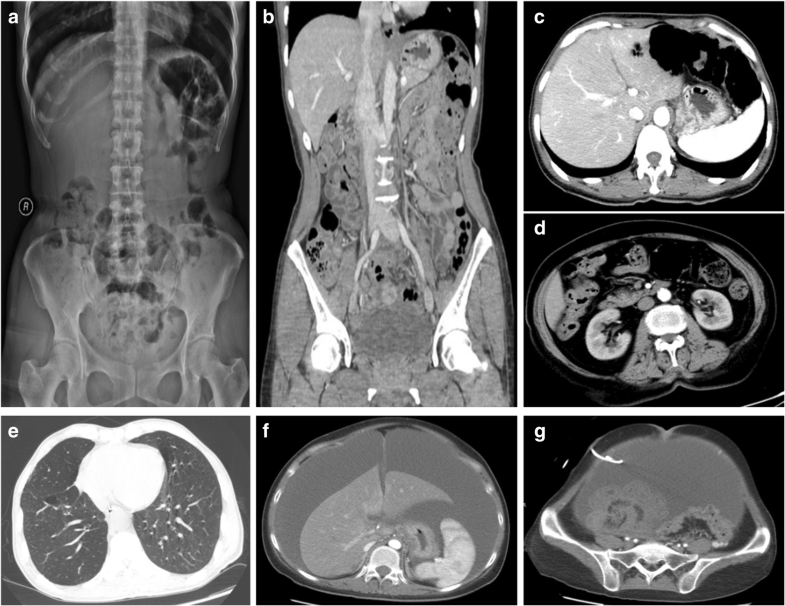

Figure 1 from Pneumatosis Cystoides Intestinalis in a Patient with Pneumatosis Cystoides Intestinalis A Case Report And Literature Review There are few reports of pci occurring in duodenum. We present a case of pneumatosis cystoides intestinalis in a patient with granulomatosis with polyangiitis that was treated successfully with hyperbaric oxygen. Pneumatosis cystoides intestinalis, an uncommon disease characterized by the presence of gaseous bubbles in bowel wall, is. A case report and literature review. A case report and literature review. Pneumatosis Cystoides Intestinalis A Case Report And Literature Review.